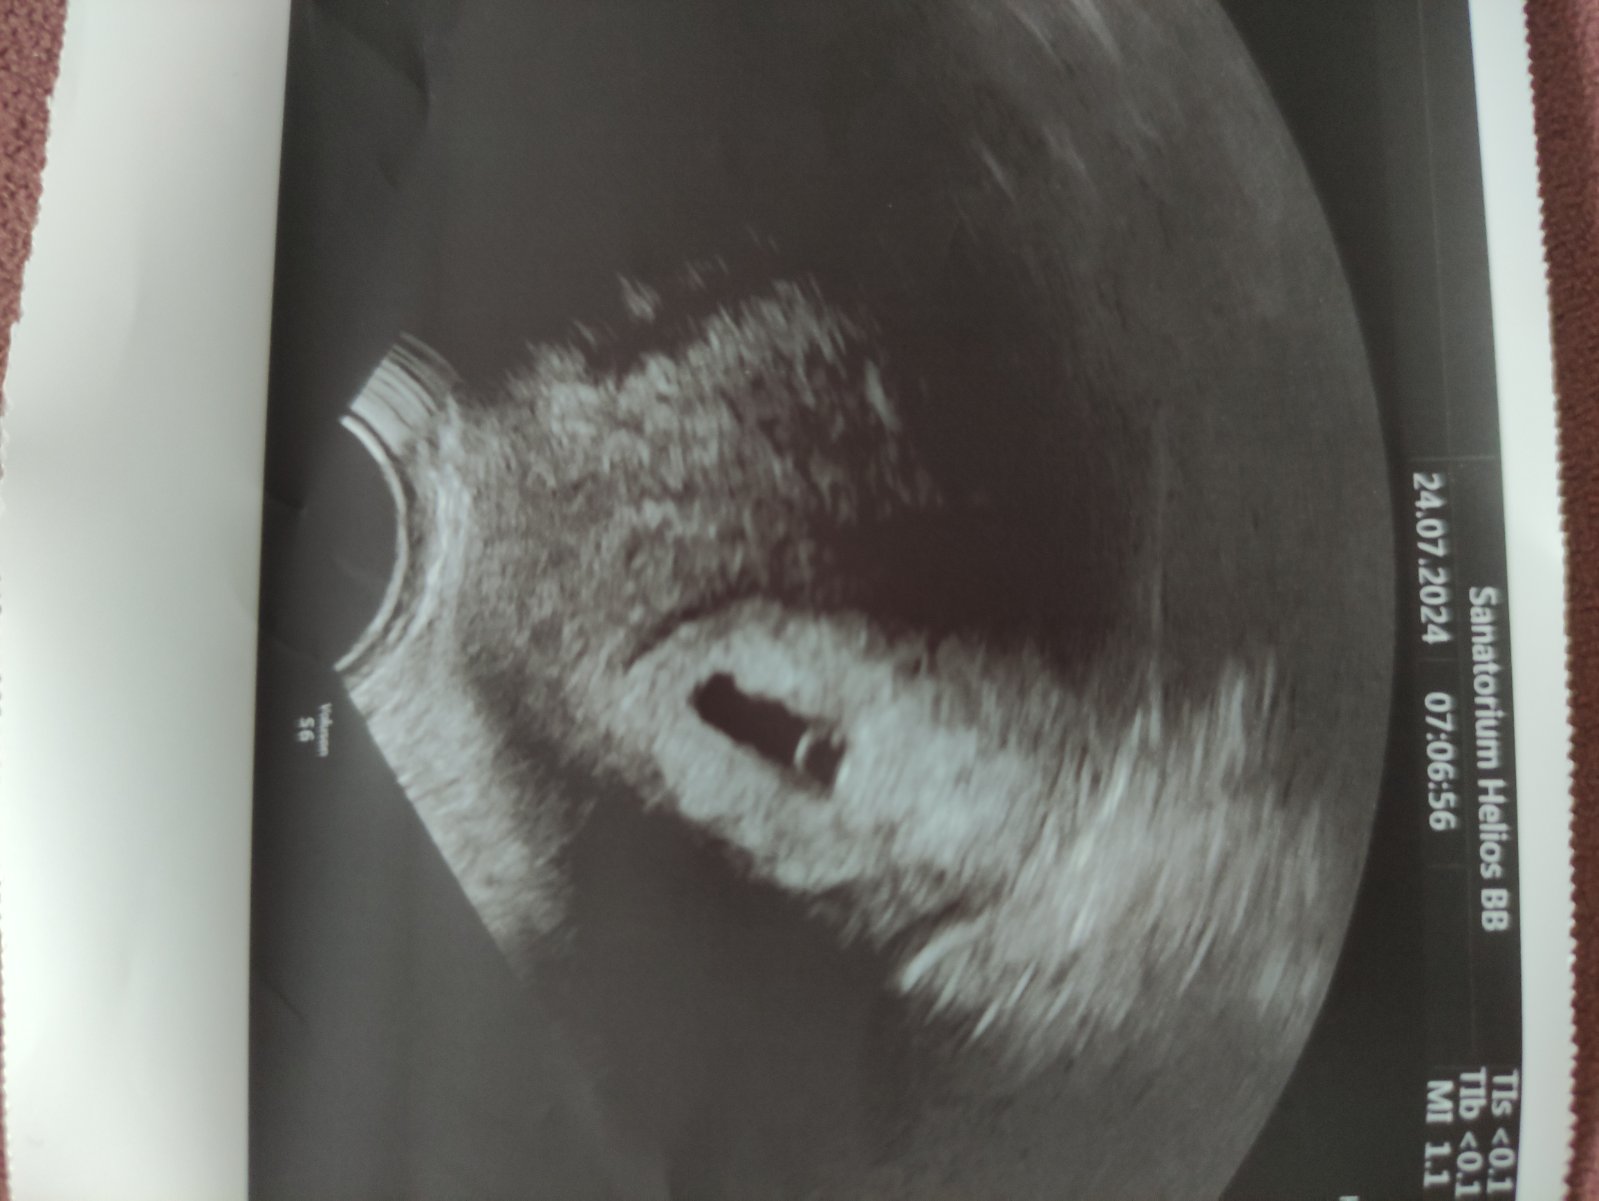

@nikadominikanika ved v niektorych car robia uz na 14dpt sona, aha toto pridavala jedba kocka do skupiny velmi pekne

Ako sa dobre pozerajú tieto obrázky 😍 prajem vám všetko iba to dobre 🍀 nech to ide len dobrým smerom ❤️